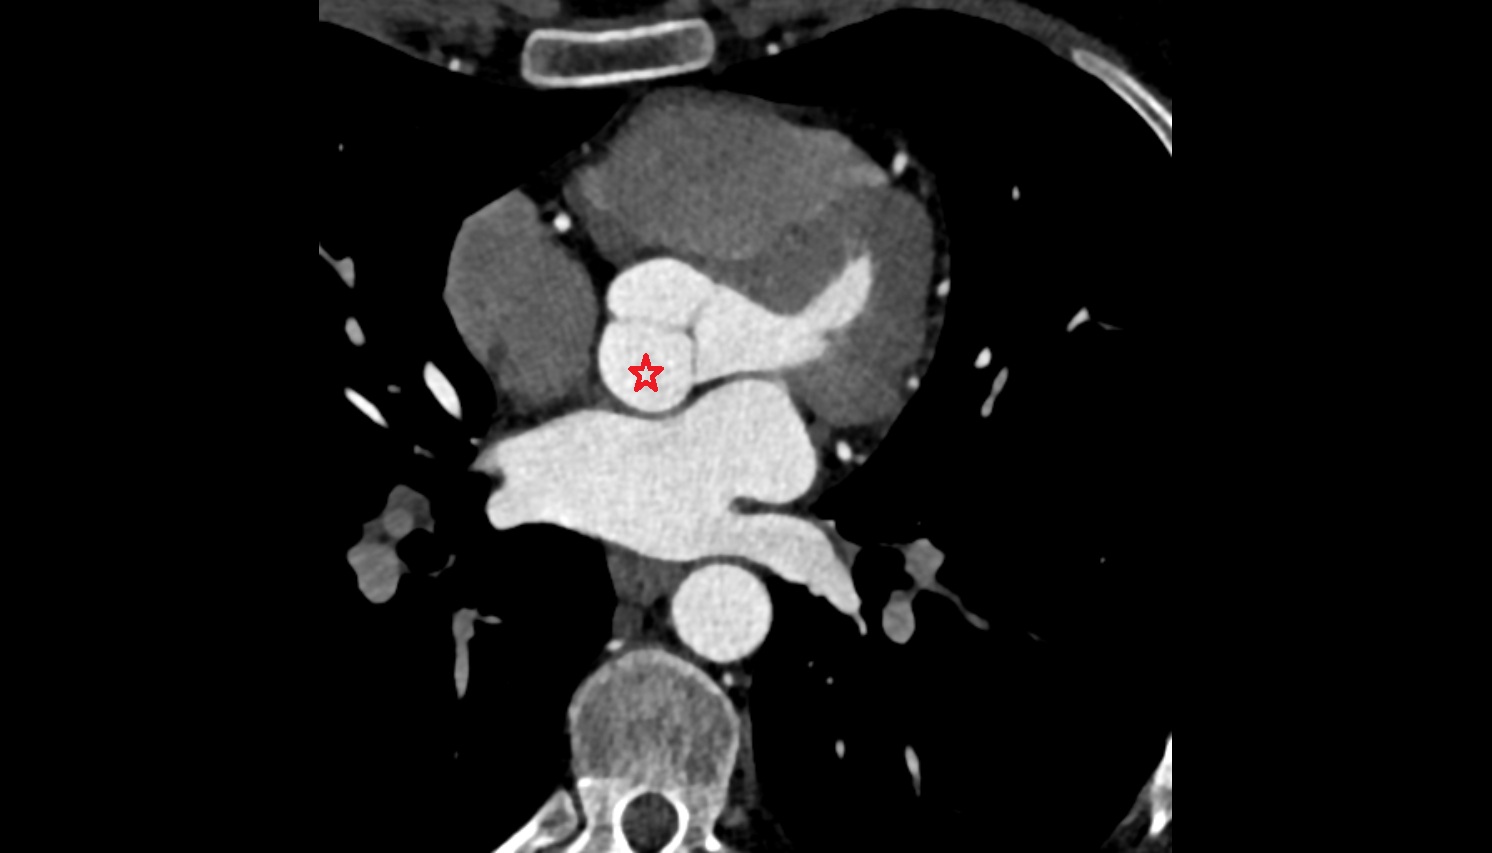

- Left main coronary artery (LMCA)

- Left anterior descending artery (LAD)

- Circumflex artery (LCx)

- Right coronary artery (RCA)